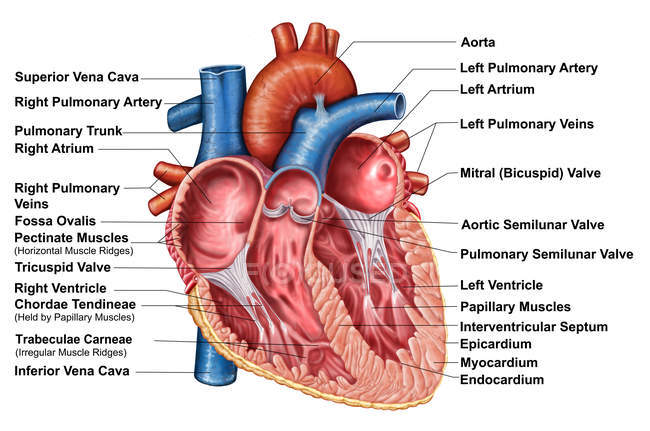

The tricuspid valve consists of three flaps or leaflets however cases are found when the tricuspid valve consists of only two or even four leaflets instead of the traditional three. The tricuspid valve lies within the right trigone.

The space in between the septal insertion of the tricuspid valve and the septal insertion of the anterior leaflet of mitral valve belongs to the membranous septum that separates the left ventricle from the right atrium.

Tricuspid valve anatomy. An appreciation of the complex and variable anatomy of the tricuspid valve is essential to unraveling the pathophysiology of tricuspid regurgitation. It is the atrioventricular valve that allows blood to flow from the right atrium to the right ventricle. Then blood exits the heart via the pulmonary artery.

Anatomy of the tricuspid valve. The tricuspid valve complex consists of the annulus leaflets right ventricle papillary muscles and chordae tendinae. Right atrioventricular valve tricuspid valve these are large veins that transport deoxygenated blood from the body back to the heart.

B the relevant anatomy shown from the front view. The tricuspid valve lies between the right atrium and the right ventricle and is placed in a more apical position than the mitral valve. The tricuspid valve has an area of 4 to 6 cm square and is located between the right atrium and the right ventricle of the heart.

The valve has anterior posterior and septal leaflets cusps the bases of which attached around the av orifice to the fibrous ring fibrous skeleton of the heart. Blood collects within the right atrium and it must flow through the tricuspid valve in order to enter the right ventricle. The tricuspid valve functions as a one way valve that closes during ventricular systole to prevent regurgitation of blood from the right ventricle back into the right atrium.

In normal heart the tricuspid valve is located slightly closer to the apex than the mitral valve. The red dotted lines show the direction of dilation of various structures in the setting of secondary tricuspid regurgitation. Unlike the aortic and mitral valve it is not possible to visualize all tv leaflets simultaneously in one cross sectional view by standard two dimensional echocardiography 2de either transthoracic or transesophageal due to the position of tv in the far field.